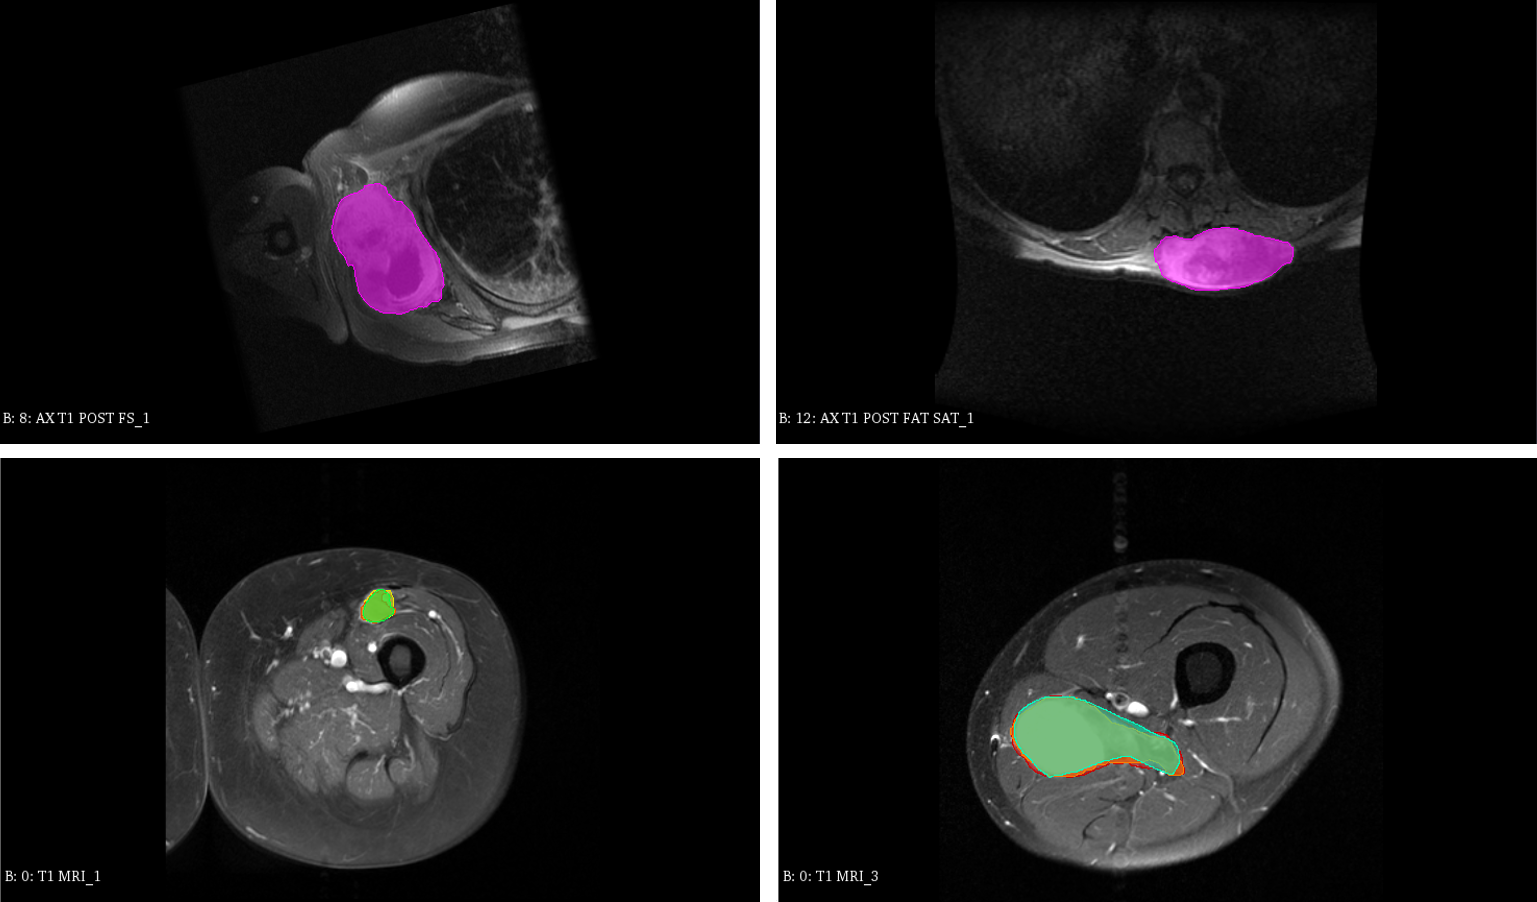

3D MRI Scan of Sarcoma Tumors (?) are sets of magnetic resonance imaging (MRI) scans of patients with sarcoma soft-tissue cancer. Clinical outcome were recorded including time-to-death censored from the day of scan acquisition and diagnosis. The goal is to classify whether the patients would survive longer than 1096 days ( 3 years) after diagnosis. In this study, censored patients due to loss of followup are considered that they survived longer than 1096 days. Pre-treatment contrast-enhanced T1-weighted 3D MRI scans are acquired from two independent cohorts of patients diagnosed with biopsy-proven soft tissue Sarcoma (STS) from two different institutes of censored institute1 (cohort1) and censored institute2 (cohort2). The acquisition is done with institutional picture archiving and communication system (PACS) standard with similar image matrix and resolutions. All patients that were less than 18 years old or were diagnosed with Kaposi or primary bone sarcomas were excluded. Included patients had sarcomas of various histologies of the extremity, trunk, or retroperitoneum. This study focused on American Joint Committee on Cancer (AJCC) version 7 stage II-III patients only, which encompasses non-metastatic patients with large (i.e. >5absent5>5 cm) and/or higher grade (i.e. >1absent1>1) tumors. Patients with image artifacts due to multiple MRI acquisitions within the tumor area were also excluded. The total number of patients in two cohorts were 200 and 72 patients, respectively. First 200 patients from cohort 1 were randomly separated into a training set of 180 images validation set of 20 images. Patients in cohort 2 were used for testing set. In all datasets, expert radiation oncologista evaluated each image for quality and manually segmented the gross tumor as ROI. Figure 3 visualize some sample in our datasets. Each scan’s ROI is resampled to have fixed resolution of 1 mm3𝑚superscript𝑚3mm^{3}. All image ROIs are then resampled again into 64×64×6464646464\times 64\times 64 voxels.

Refer to caption

Figure 3: Example visualization of sample in MRI dataset with segmented ROI defined by expert. Top: samples from cohort1 patients. Bottom: samples from cohort2 patients.